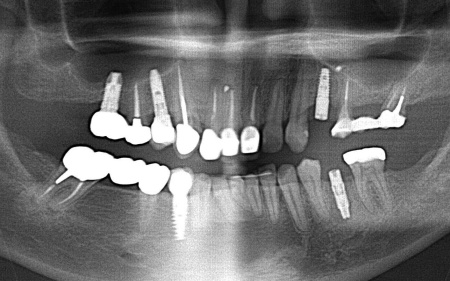

レントゲン撮影をして痛みの原因を詳しく検査したところ、左上下奥歯の歯根が割れており、その影響で痛みが出ていると考えられました。

以上のことから、温存が難しいと判明している左上奥歯は抜き、左下奥歯は被せ物を取り外して内部を確認したうえで、適切な処置を行うことが望ましいと診断しました。

診断結果をお伝えし、患者様の了承を得たうえで左下奥歯の被せ物を外したところ、レントゲン検査での診断どおり、歯根が割れていることが確認できました。

そのため、患者様には左上下奥歯とも温存が難しい旨を説明し、抜歯に同意いただきました。

患者様は、以前当院で人工歯根を顎の骨に埋入して歯を装着するインプラント治療を受けていたため、今回も左上下奥歯ともインプラント治療を希望されています。

続いてインプラント手術を実施し、インプラントを正しい位置と角度で顎の骨に埋め込みました。